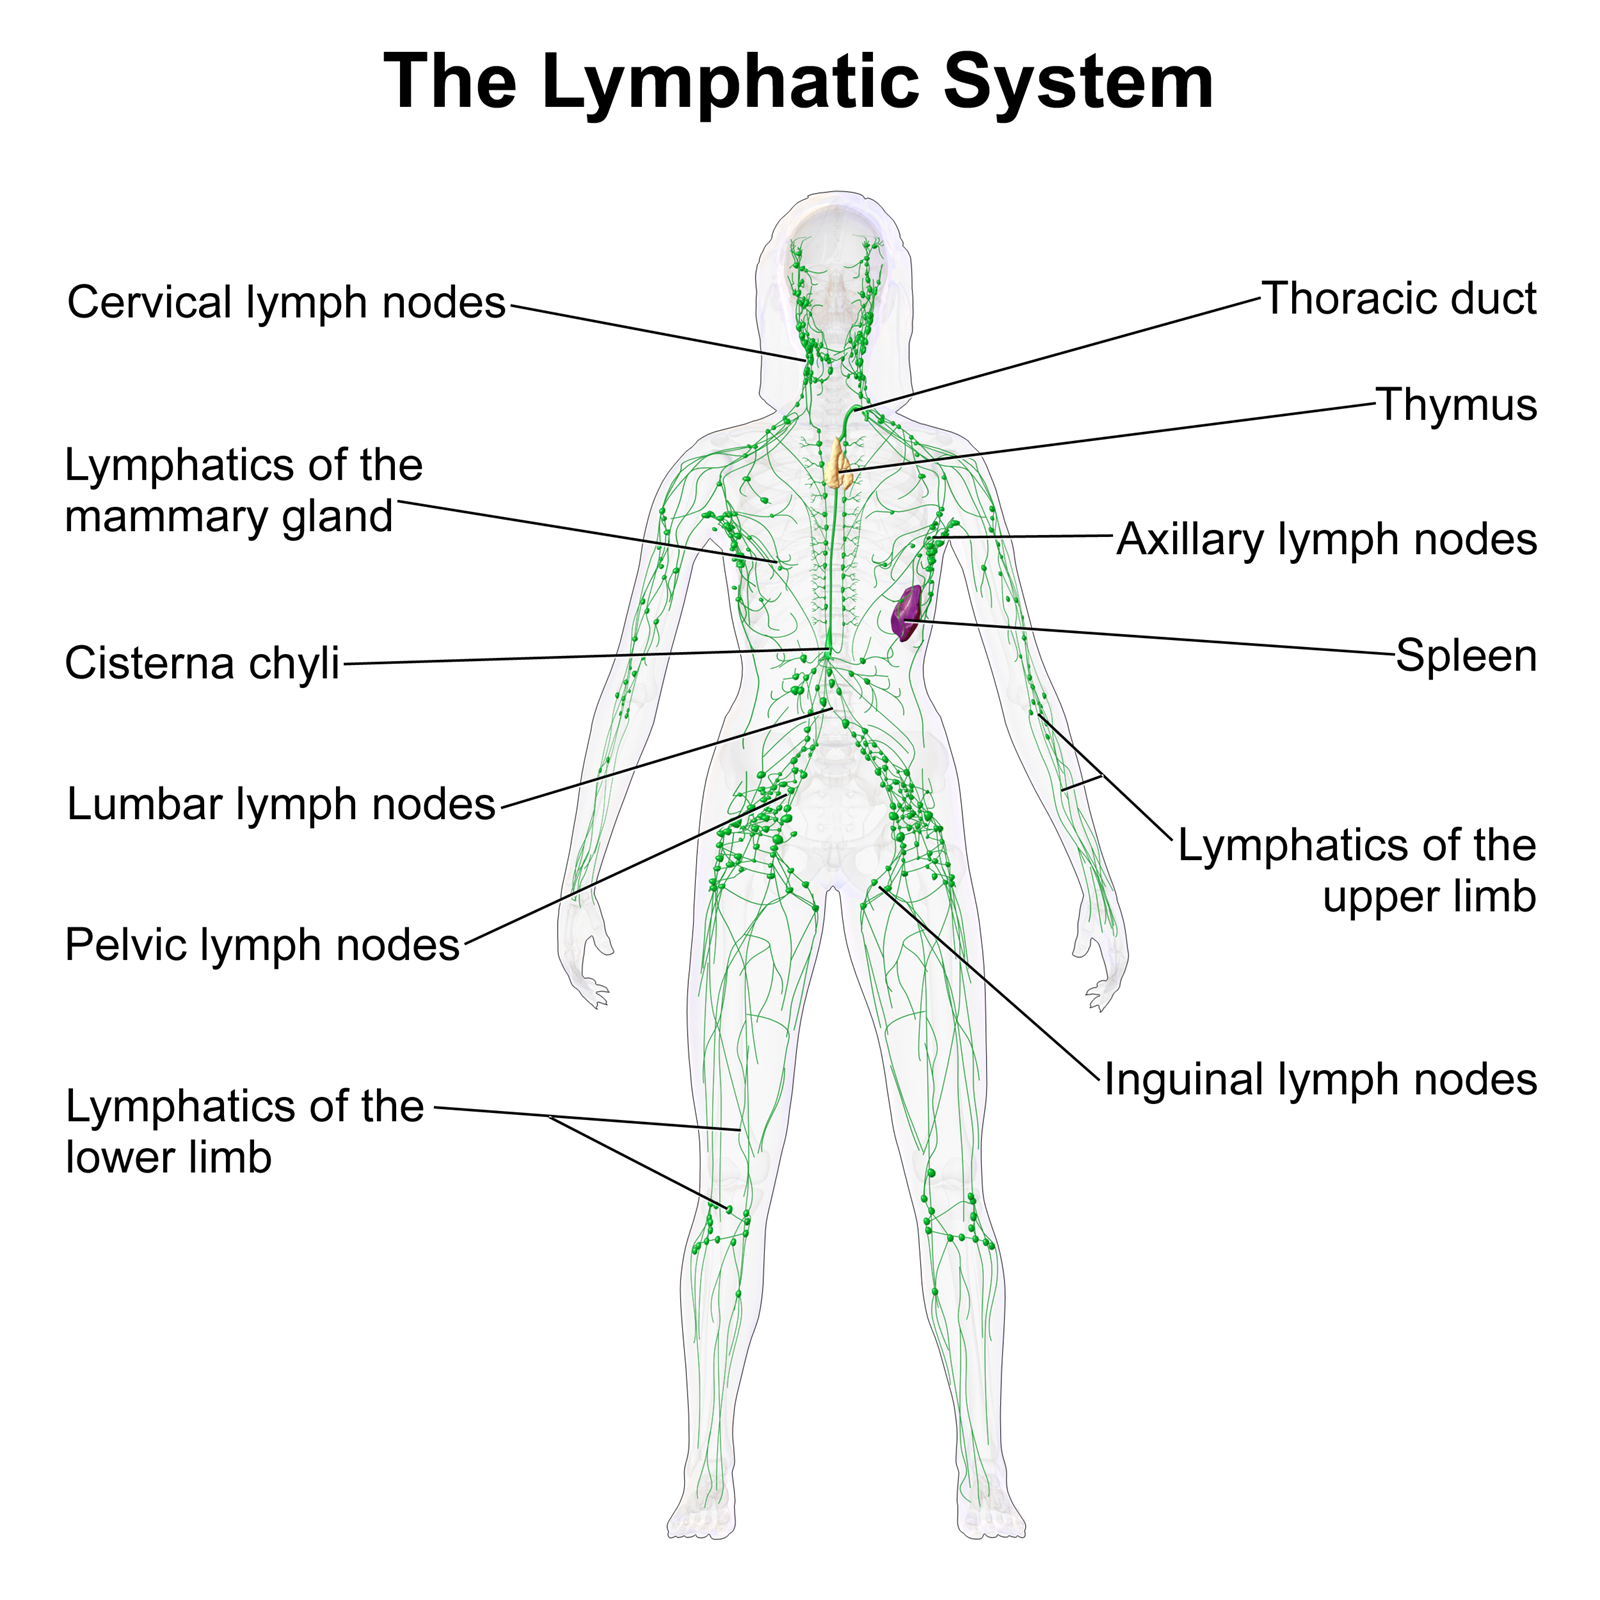

Map Of Lymph Nodes In Human Body

mungfali.com

mungfali.com

The Lymphatic System | BIOL 141 | Thoracic, Lymphatic, Lymphatic System

www.pinterest.com

www.pinterest.com

lymph lymphatic nodes system abdominal wall lymphatics superficial functions thoracic trunk vessels located ducts major direction veins anterior parts structure

7. The Lymphatic System - SimpleMed - Learning Medicine, Simplified

www.simplemed.co.uk

www.simplemed.co.uk

lymph lymphatic nodes

Lymphatic System

biology-diagrams.blogspot.com

biology-diagrams.blogspot.com